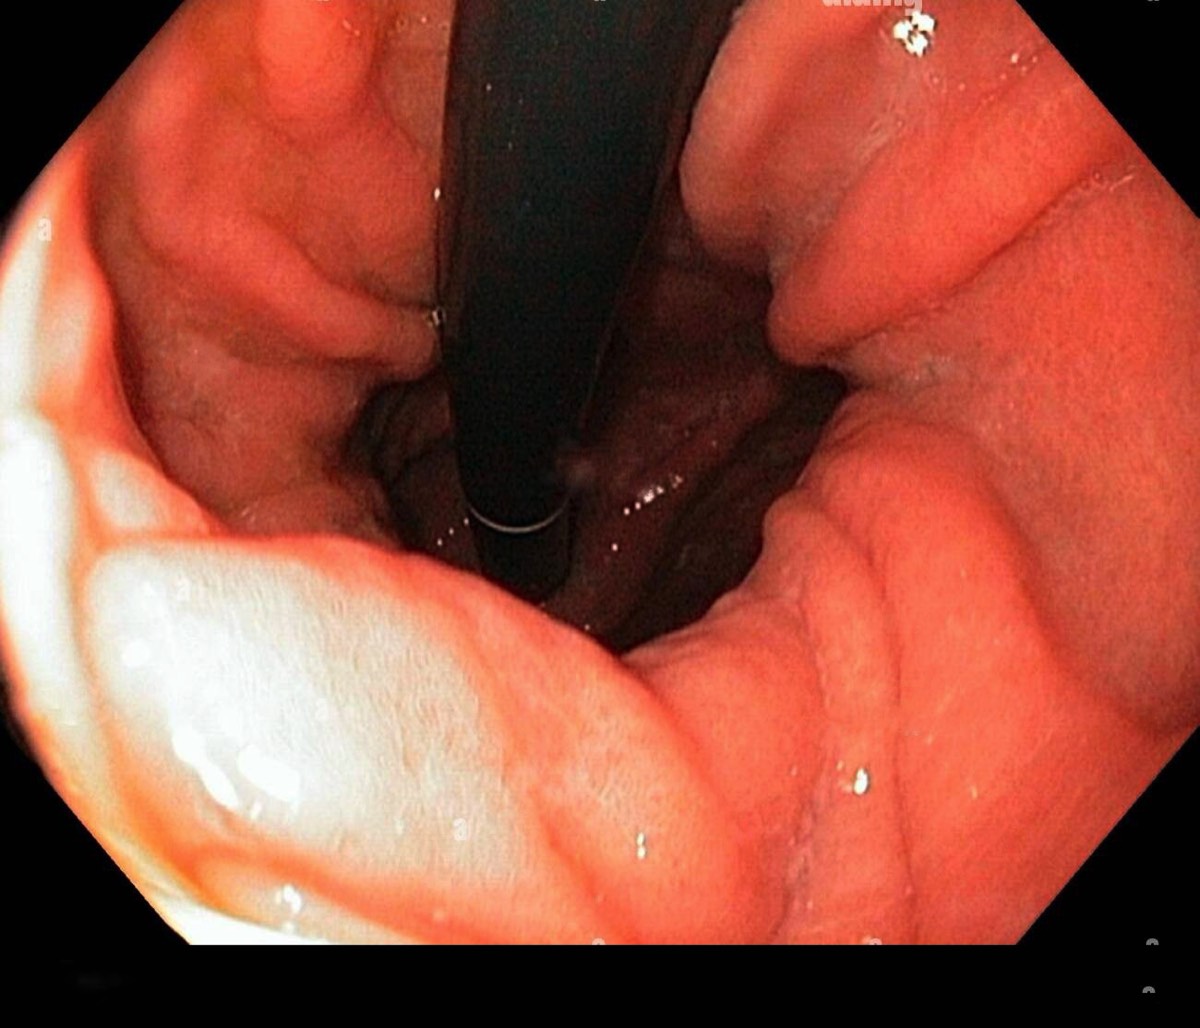

2) Μια ενδοσκοπικη μελέτη (γαστροσκοπηση) χρήσιμη στη διερεύνηση οισοφάγου και στομάχου .

Εικονες απο αξονικη τομογραφια και ενδοσκοπηση

Οισοφάγος Barrett

Αντικατάσταση τμήματος πλακώδους επιθηλίου από κυλινδρικό (εντερική μεταπλασία) Ο κίνδυνος για καρκίνο του οισοφάγου είναι αυξημένος κατα 40 φορές .